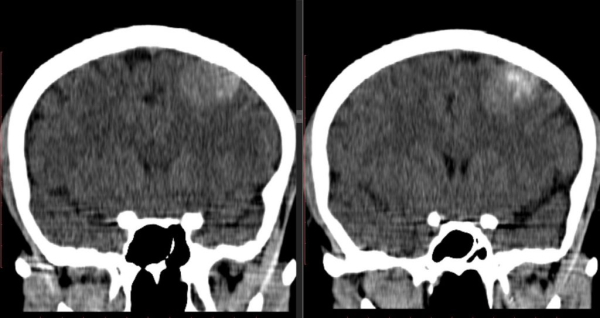

• Компьютерная томография. Информативный метод диагностики, который дает двухмерные снимки сформированной внутри патологии.